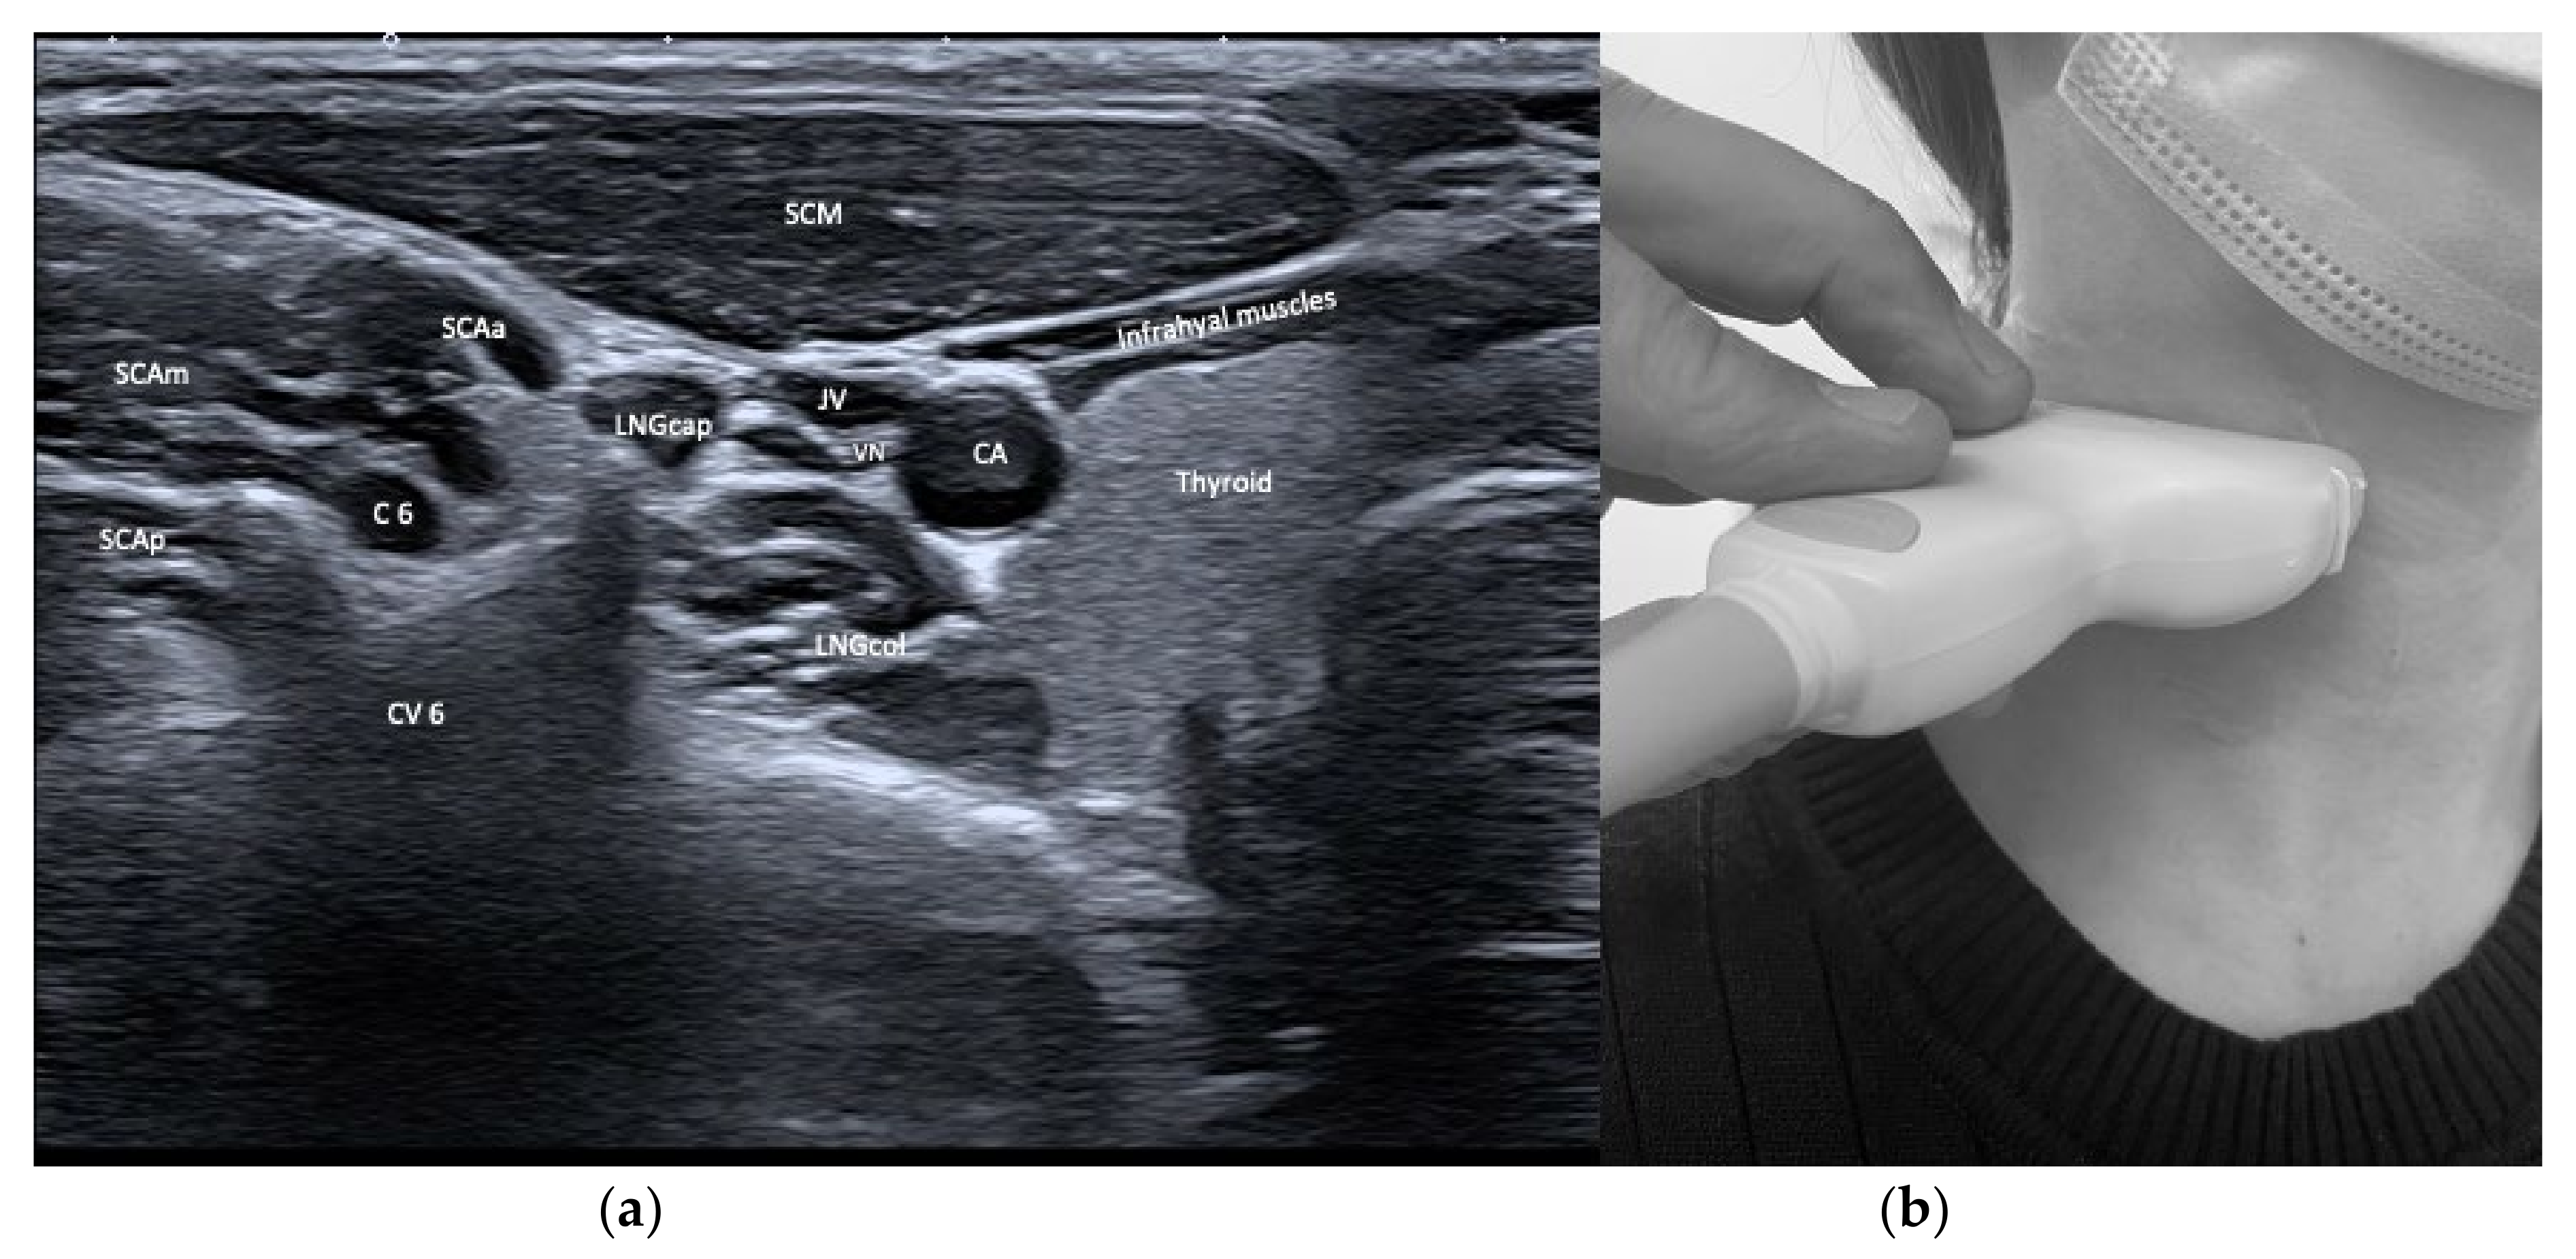

| Longus capitis (LNGcap) | Anteflexion of head and neck | +++ | +++ | Carotid artery, jugular vein, vagus nerve, phrenic nerve | Authors recommend a transoral injection |

| Longus colli (LNGco) | Anteflexion of neck | +++ | +++ | Carotid artery, jugular vein, vagus nerve, phrenic nerve | Authors recommend a transoral injection |

| Scalenus anterior (SCAa) | Anteflexion of neck | +++ | +++ | Thyroid, carotid artery, brachial plexus, phrenic nerve, lung | |